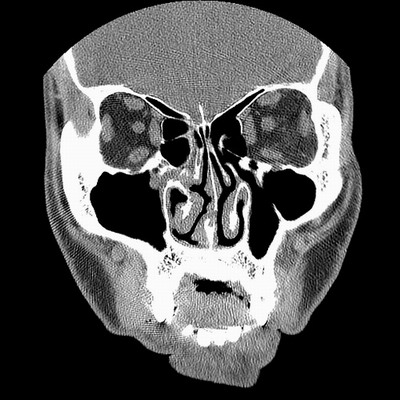

男,38岁,鼻塞、头痛2个月,要求鼻窦ct检查。

右侧上颌窦、蝶窦、筛窦、额窦及左侧上颌窦慢性炎症。

右侧鼻中隔左偏,右侧上颌窦、筛窦、额窦慢性炎性病变。右侧上颌窦开口粘膜增厚。

1)副鼻窦炎。2)右侧中鼻道及总鼻道粘膜息肉样变。3)双侧中下鼻甲肥大。4)鼻中隔轻度左突偏曲。